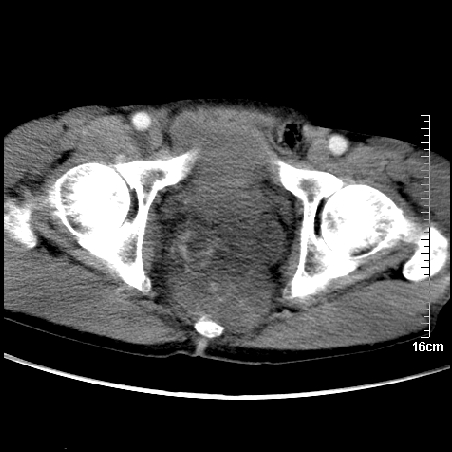

增强:

1、骶尾部巨大软组织肿块,部分骶尾骨以被软组织肿块代替,呈不规则侵蚀;病变突向盆腔内;增强扫描病变呈不均质强化;首先考虑脊索瘤。不支持的一点就是病变内无钙化。

2、发生于骶尾椎者须与骨巨细胞瘤鉴别,骨巨细胞瘤一般发在上疗骶椎,肿瘤内无钙化,一般无侵袭性生长的表现。